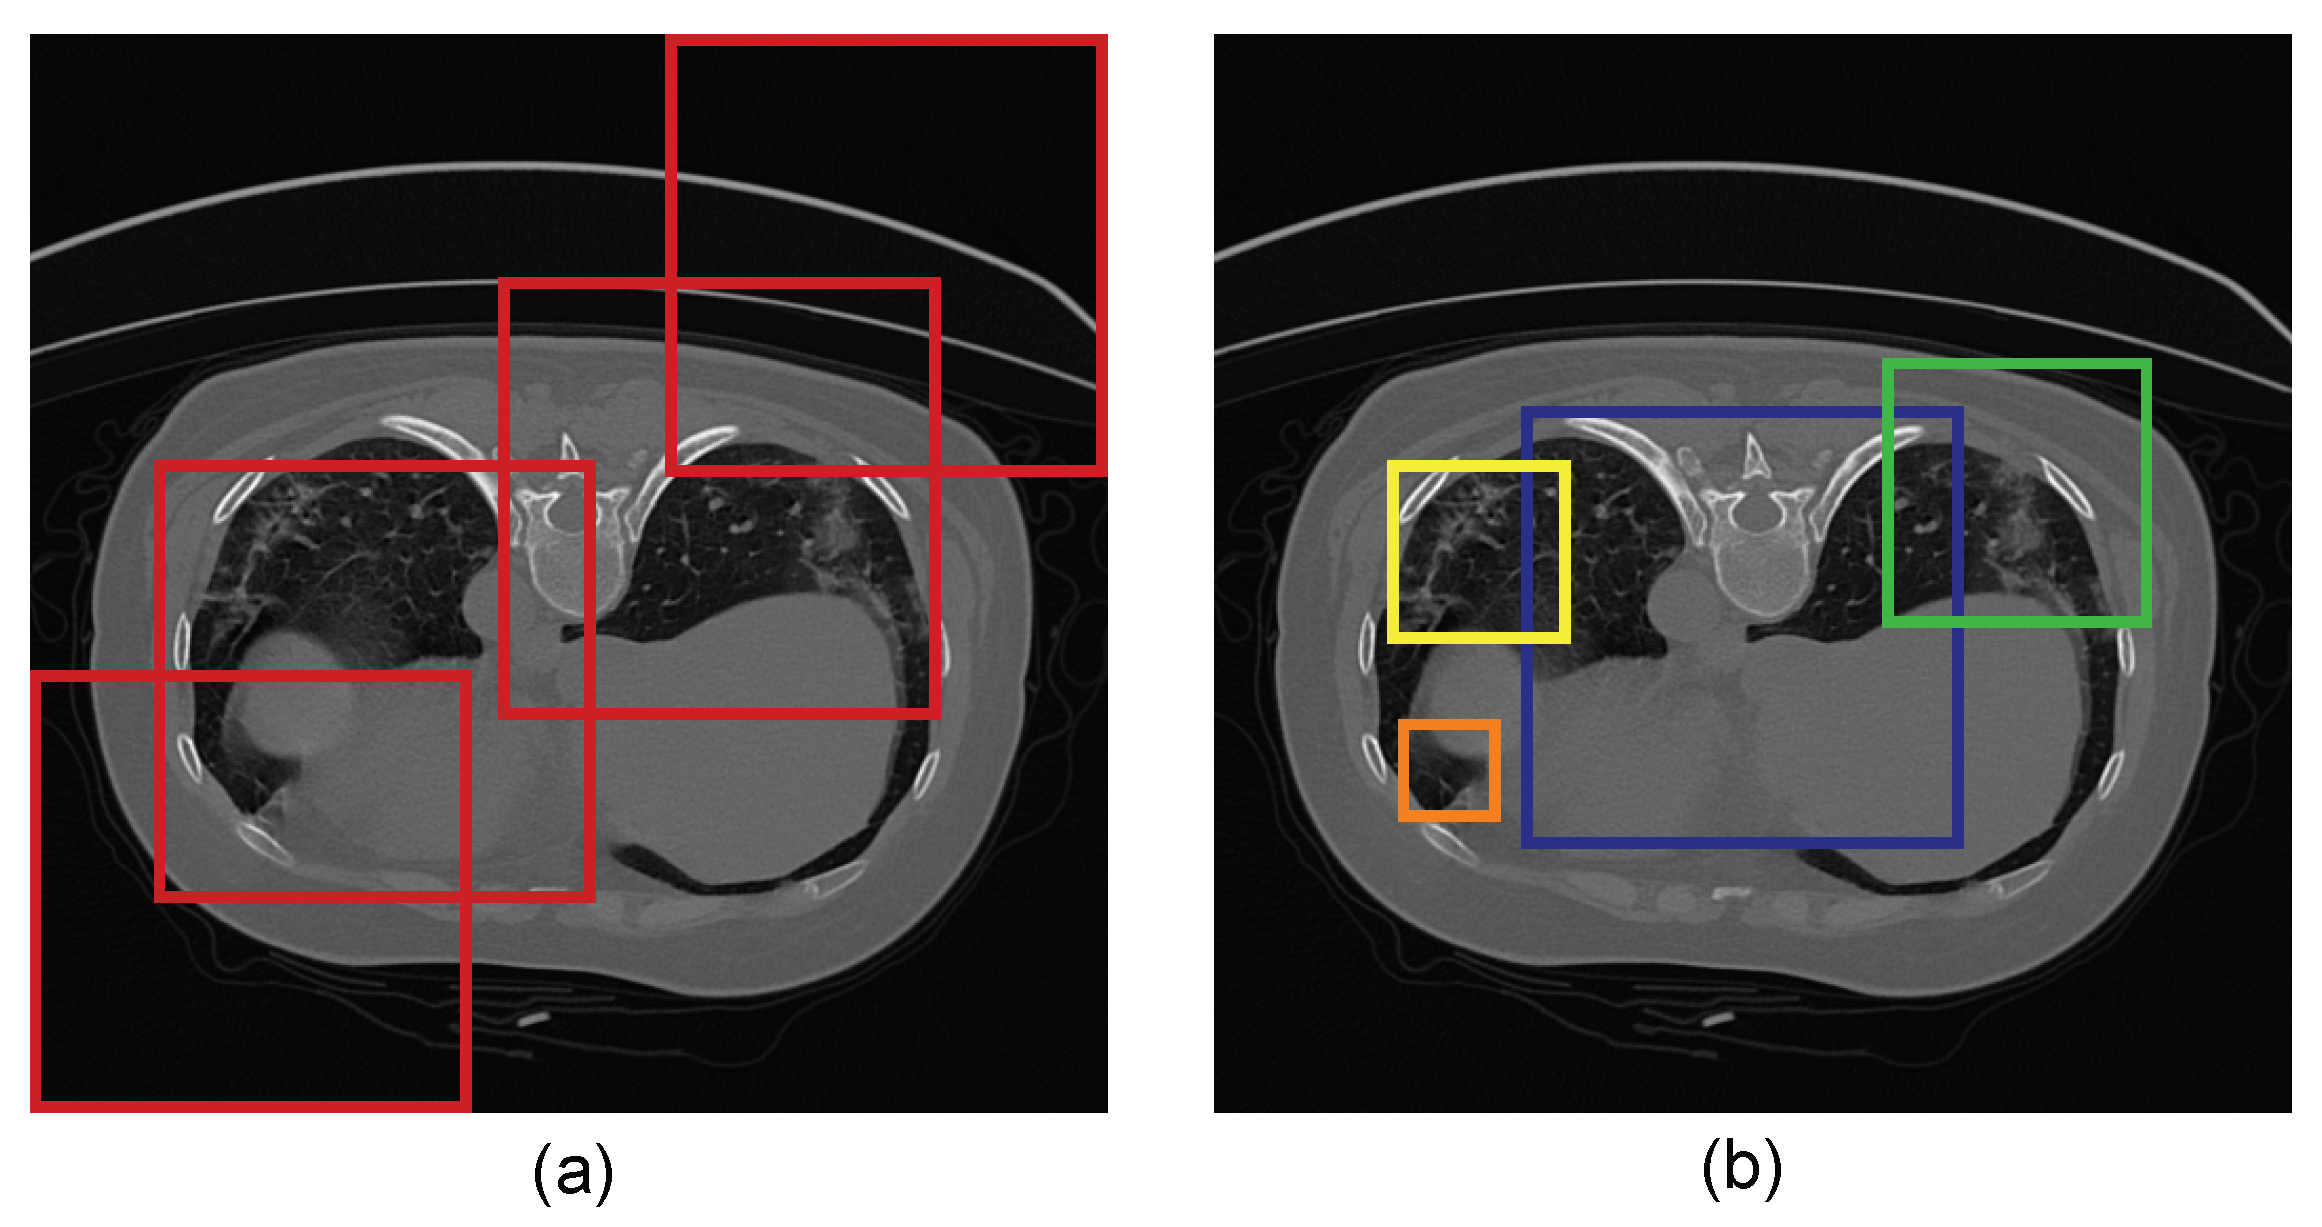

3.1.1. COVID-19 Lung CT Dataset

3.1.2. Data Augmentation and Parameter Setting